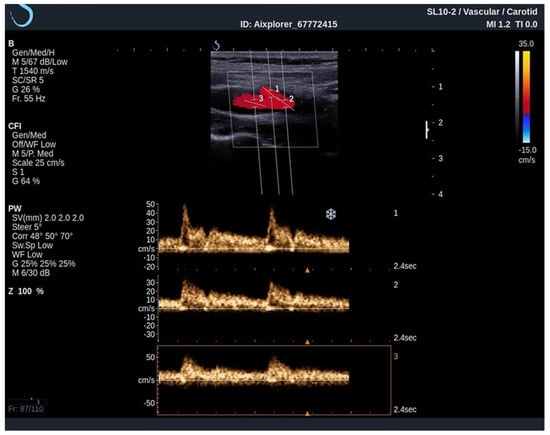

When performing an UltraFast Doppler examination, a single-shot acquisition mode is usually initiated from the conventional color Doppler imaging mode. After that, a range of UltraFast Doppler data is acquired (typically 2 to 4 s), and the picture is frozen. The examiner can then review the UltraFast color flow data, review a single or multiple frames offering the best image visualization of the flow characteristics of interest and simultaneously perform a retrospective spectral analysis of the color box. Furthermore, using UltraFast™ Doppler, a short clip of not only one, but multiple regions of interest can be obtained, providing a more precise comparison of both mean and peak flow velocity originating from the same cardiac cycle (Figure 4) [21].

Figure 4. An UltraFast™ Doppler examination of the bifurcation of the carotid artery. Several measurements can be performed independently of each other with a high degree of reliability since the acquisition is made during the same cardiac cycle. In this example, spectra from the ICA (3) and ECA (2) are analyzed simultaneously, one can differentiate the ICA from the ECA on the basis of spectral morphology with ECA demonstrating a high-resistance spectrum and the ICA demonstrating a low-resistance spectrum.